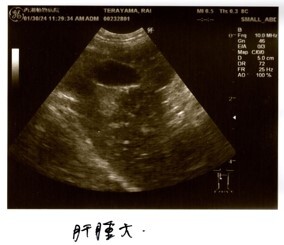

炎症の値は振り切れ、貧血、黄疸、リンパ節腫大、化膿性肉芽腫炎症という検査結果から、FIPを強く疑う。との診断でした。